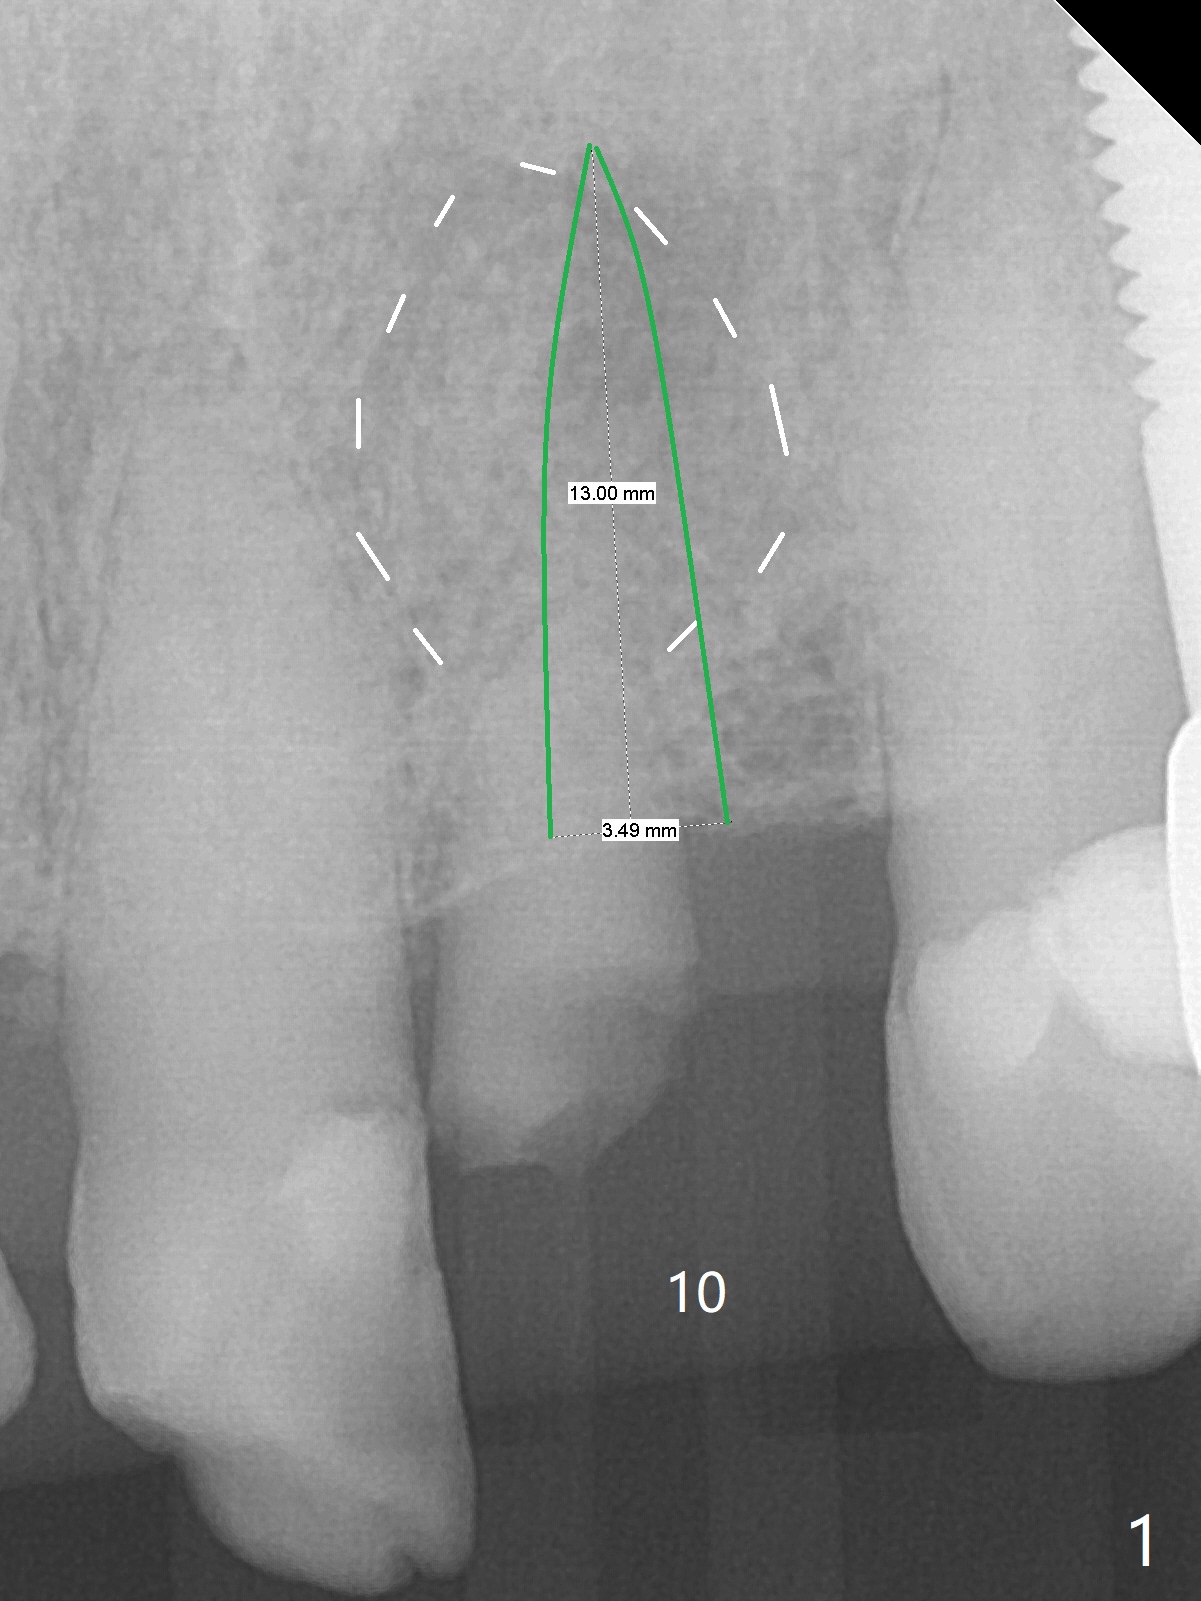

A 88-year-old man fractures the upper lateral incisor (microdontia) (Fig.1). Because of the labial concavity (white dashed line), it appears that an implant smaller than 3.5 mm is appropriate for the site. Clinical examination and CBCT confirm the concavity (Fig.2,4 *). Since the tooth deviates mesial, osteotomy should be initiated distopalatal (Fig.1,4).